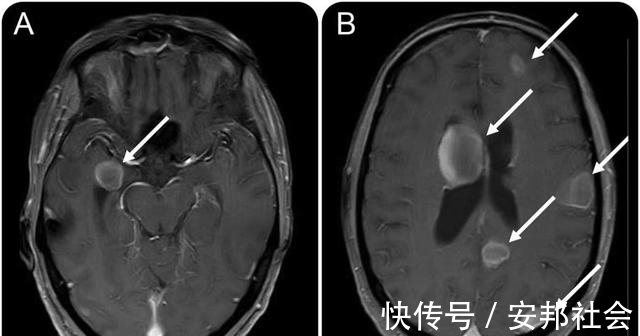

1、转移就无法根治有很多人很不理解为什么转移了就不能根治,把肺部肿瘤病灶和转移病灶一起切除不就行了吗?其实这是行不通的,因为肺癌只要转移到其他部位生长出肿瘤,说明血液和淋巴液中就有癌细胞,即使把所有的瘤体全部切除,血液中的癌细胞也无法完全清除,而手术对身体的打击会降低免疫力,使血液中的癌细胞会更加容易的在全身各个器官生长并形成新的瘤体,加速病情的发展。2、肺部转移也是转移,大部分就是晚期肺分五叶,右三左二,一个肺叶发生癌肿,转移到其他肺叶甚至是对肺,一般不是通过支气管流淌过去的,而是进入血液流淌至对肺的,所以即使是同肺不同叶出现病灶,也算是转移,同肺叶内有病灶,则算是中期,虽然不是晚期,也大部分很难根治了。3、为什么有些人没有检查到转移而行根治性手术,术后很快复发转移呢?这个问题是很多人难以理解的,明明是早期,也做了根治性手术,术后为什么很快就复发转移了呢,这主要是因为目前的科技手段还无法准确的判断血液中是否有尚未形成转移灶的“漂流”癌细胞,有些早期癌症就发生了癌细胞脱落,这些癌细胞在血液循环过程中大部分会被免疫细胞杀灭,但少量的癌细胞仍有非常小的几率存活下来并在最终形成肿瘤转移灶,这是有些早期肿瘤手术后也要做化疗的原因,也是少数早期患者根治性手术后复发转移的原因。